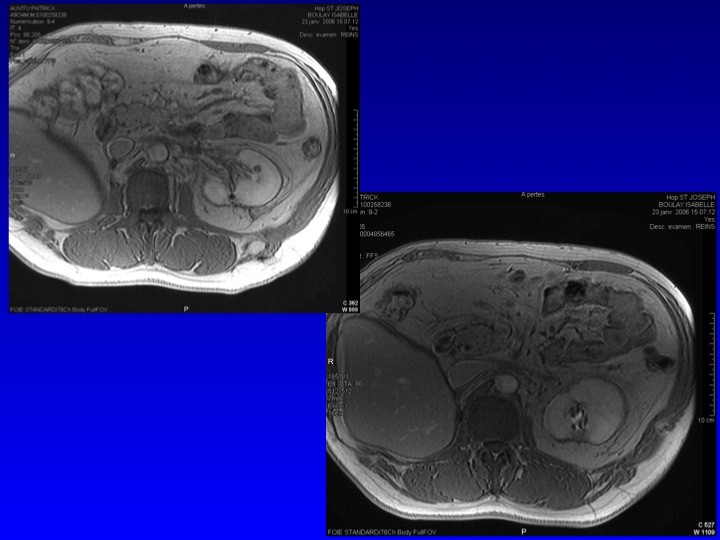

- Nos échecs

Nathalie RIOUX LECLERCQ (Rennes), Nicolas GRENIER (Bordeaux), Hervé BAUMERT (Paris)